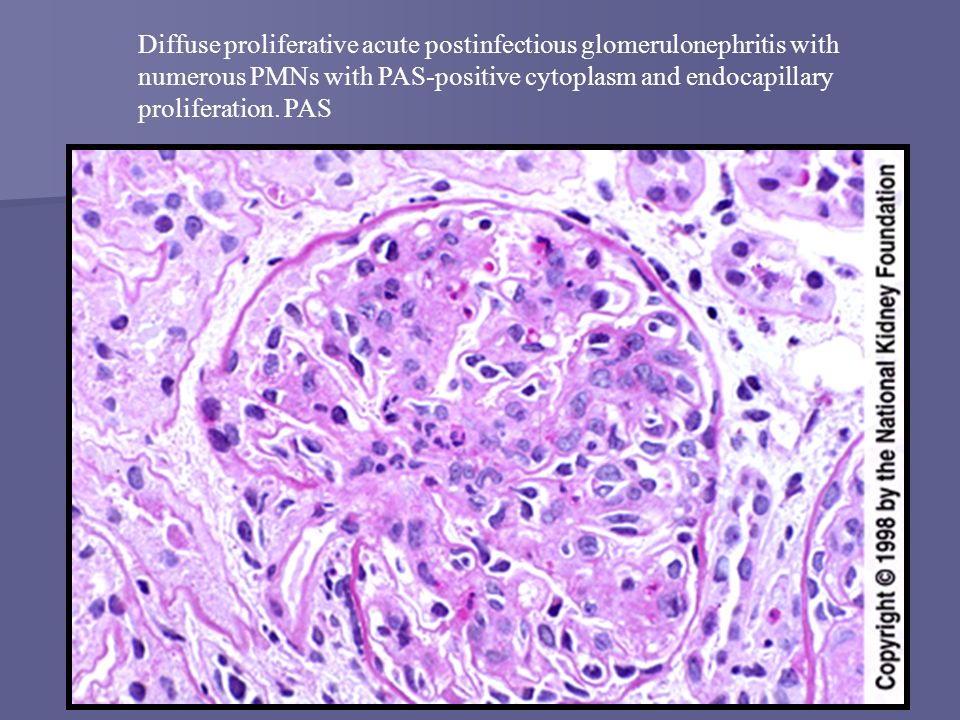

Механизм остро го диффузного гломерулонефрита